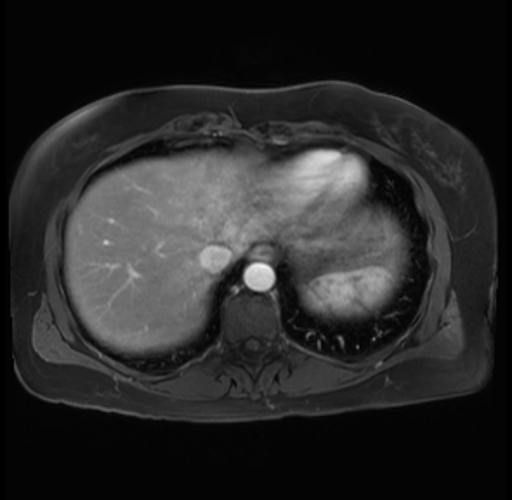

Imaging Analysis

Look through the patient's CT scan to identify any areas of concern for the necessary procedure.

Based on your CT findings, which issue(s) are present and would give reason for "planned slowing down moment(s)" in this case?